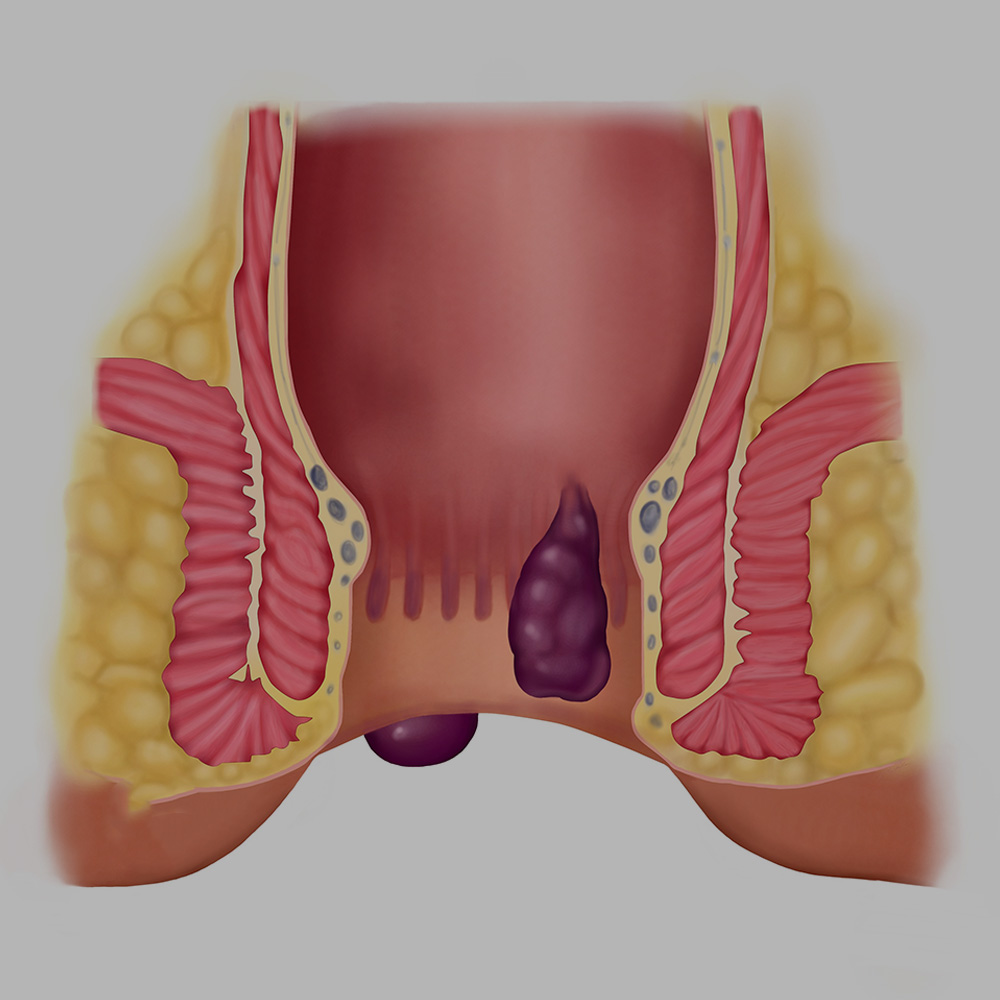

Hemoroid "Basur"